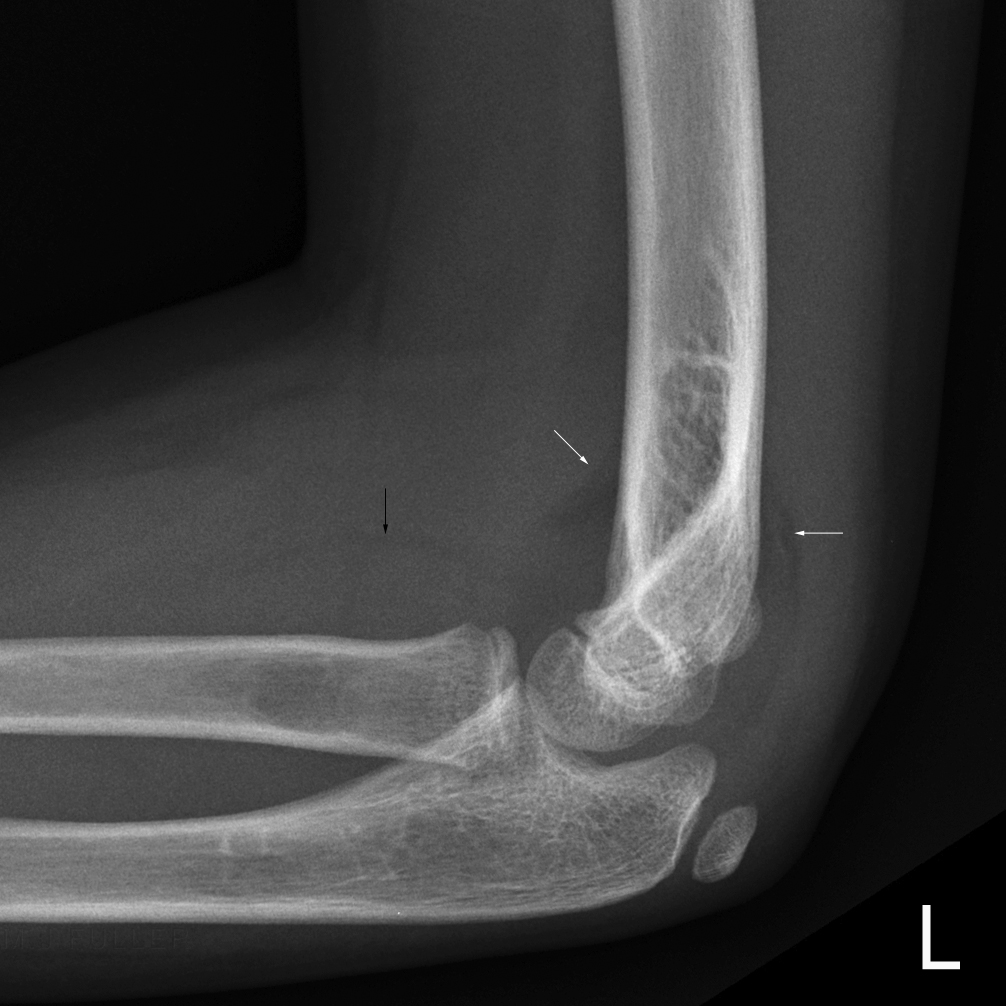

humeral line anterior elbow supracondylar pediatric fractures normal radiology fracture humerus radiopaedia capitellum angle capitulum joint case types injuries occult

elbow ray radial fracture head normal alignment line anterior humeral coreem

elbow forearm normal lateral alignment anterior capitellum radiograph interpreting radiographs fracture supracondylar intersect

elbow line anterior normal radiocapitellar humeral fractures adults lateral radiograph dislocations imaging

humeral radiocapitellar elbow radiographic

elbow humeral fracture supracondylar forearm capitellum radiographs interpreting intersect

elbow xrays humeral radiocapitellar emdocs fracture

elbow xrays anterior humeral radiocapitellar emdocs fracture

humeral lateral elbow rogers

radiopaedia line humeral anterior radiology

capitellum dislocation elbow pediatric through drawn lateral anterior humeral pass should line

elbow aliem fracture xray supracondylar year old anterior humeral pv line arrows card pain left sight diagnose male injuries sutures

Anterior humeral line. Pediatric humeral fracture. Elbow injuries